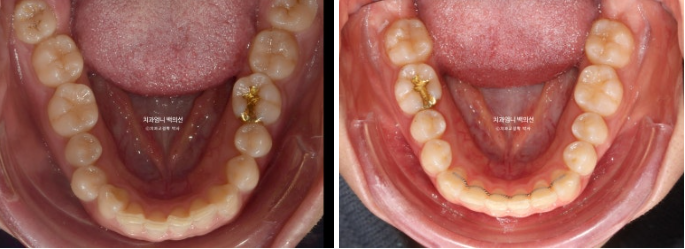

치료 후 입안사진 보겠습니다.

25.01

25.02

좋은 교합입니다.

유지장치 까지 붙은 모습입니다.